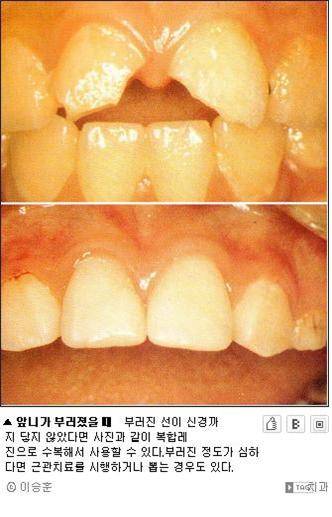

치아가 부러졌을 때는 부러진 선이 어디까지 도달 했느냐에 따라 예후가 천차만별이다.

경미할 경우 주변부를 가볍게 갈아내는 정도의 진료만 받으면 되지만 심한 경우 치아를 뽑아야 한다.

부러진 선이 치아 안의 신경까지 도달했다면 환자는 강한 통증을 느끼는 것이 대부분이기에 이가 부러졌을 때 통증이 크지 않다면 일단은 응급으로 근관치료를 할 필요는 없다고 봐도 좋다.

하지만 치아가 단순히 부러졌는지 아니면 빠지거나 움직였기에 응급한 치료가 필요한지의 여부를 일반인이 정확히 진단하는 것은 힘든 일이니까 일단 응급실을 방문하는 것이 안전하다.